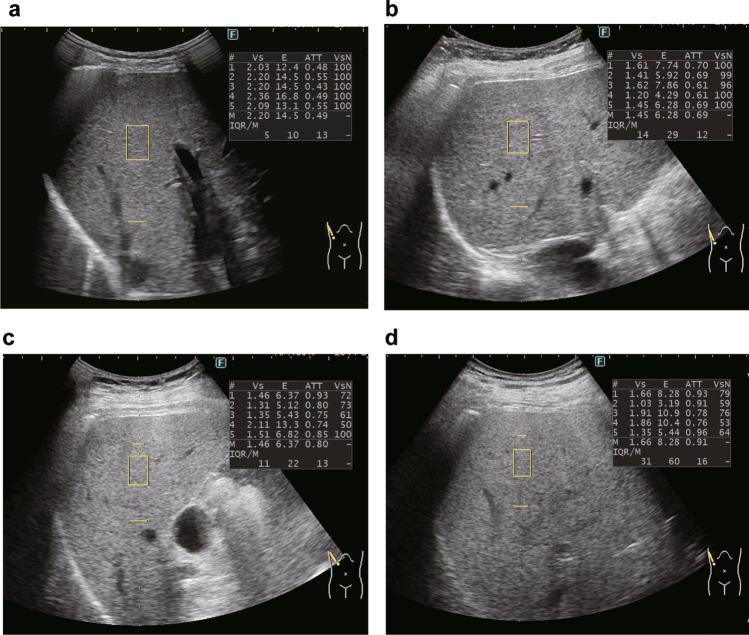

Several preliminary reports have suggested the utility of ultrasound attenuation coefficient measurements based on B-mode ultrasound, such as iATT, for diagnosing steatotic liver disease. Nonetheless, evidence supporting such utility is lacking. This prospective study aimed to investigate whether iATT is highly concordant with magnetic resonance imaging (MRI)-based proton density fat fraction (MRI-PDFF) and could well distinguish between steatosis grades.

A cohort of 846 individuals underwent both iATT and MRI-PDFF assessments. Steatosis grade was defined as grade 0 with MRI-PDFF < 5.2%, grade 1 with 5.2% MRI-PDFF < 11.3%, grade 2 with 11.3% MRI-PDFF < 17.1%, and grade 3 with MRI-PDFF of 17.1%. The reproducibility of iATT and MRI-PDFF was evaluated using the Bland-Altman analysis and intraclass correlation coefficients, whereas the diagnostic performance of each steatosis grade was examined using receiver operating characteristic analysis.

The Bland-Altman analysis indicated excellent reproducibility with minimal fixed bias between iATT and MRI-PDFF. The area under the curve for distinguishing steatosis grades 1, 2, and 3 were 0.887, 0.882, and 0.867, respectively. A skin-to-capsula distance of ≥ 25 mm was identified as the only significant factor causing the discrepancy. No interaction between MRI-logPDFF and MRE-LSM on iATT values was observed.